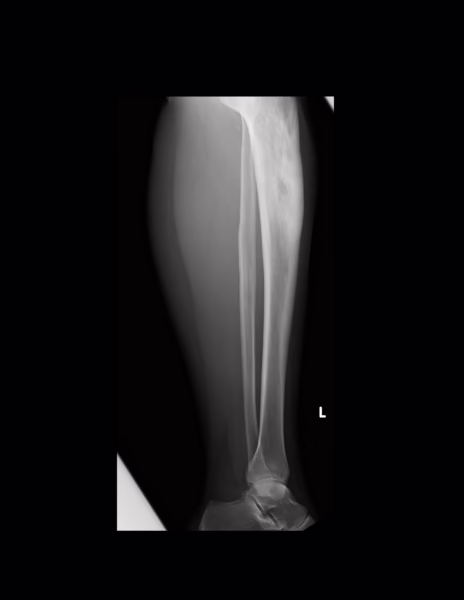

Los tejidos blandos muestran una densidad homogénea.

Cambios en la densidad ósea tibial, disminución en la densidad a nivel de la epífisis proximal, acentuación de la trabécula ósea, engrosamiento cortical y aumento en la densidad en la diáfisis proximal y media, con áreas radiolúcidas centrales irregulares, no hay evidencia de disrupción cortical.

Disminución leve del espacio articular femorotibial externo, el espacio articular tibioastragalino conservado.

IMPRESION DIAGNOSTICA:

Cambios en la densidad ósea de la tibia, disminución en la densidad en la epífisis proximal y acentuación de la trabécula ósea, engrosamiento cortical y aumento en la densidad en la diáfisis proximal y media con áreas radiolúcidas centrales irregulares, no hay evidencia de disrupción cortical.

Disminución leve del espacio articular femorotibial externo.

HALLAZGOS:

- Engrosamiento y reacción perióstica irregular de la cortical ósea con imagen radiolucida en su interior rodeada por imagen radiopaca en anillo en relación centro necrótico y formación de hueso hueso nuevo en relación a secuestro e involucro.

- Región proximal peroné normales.

- Región diafisaria distal y metafisaria de la tibia y peroné normales.

- Maléolo medial y lateral morfológicamente normales.

- Astrágalo y calcáneo de bordes regulares, sin alteraciones.

- No se evidencian lesiones líticas o blásticas.

- Adecuada relación articular tibio astragalina.

- Partes blandas sin evidencia de aumento de grosor.

IMPRESIÓN DIAGNOSTICA:

- Datos a favor de osteomielitis crónica a nivel del tercio proximal de la diáfisis de tibia izquierda.